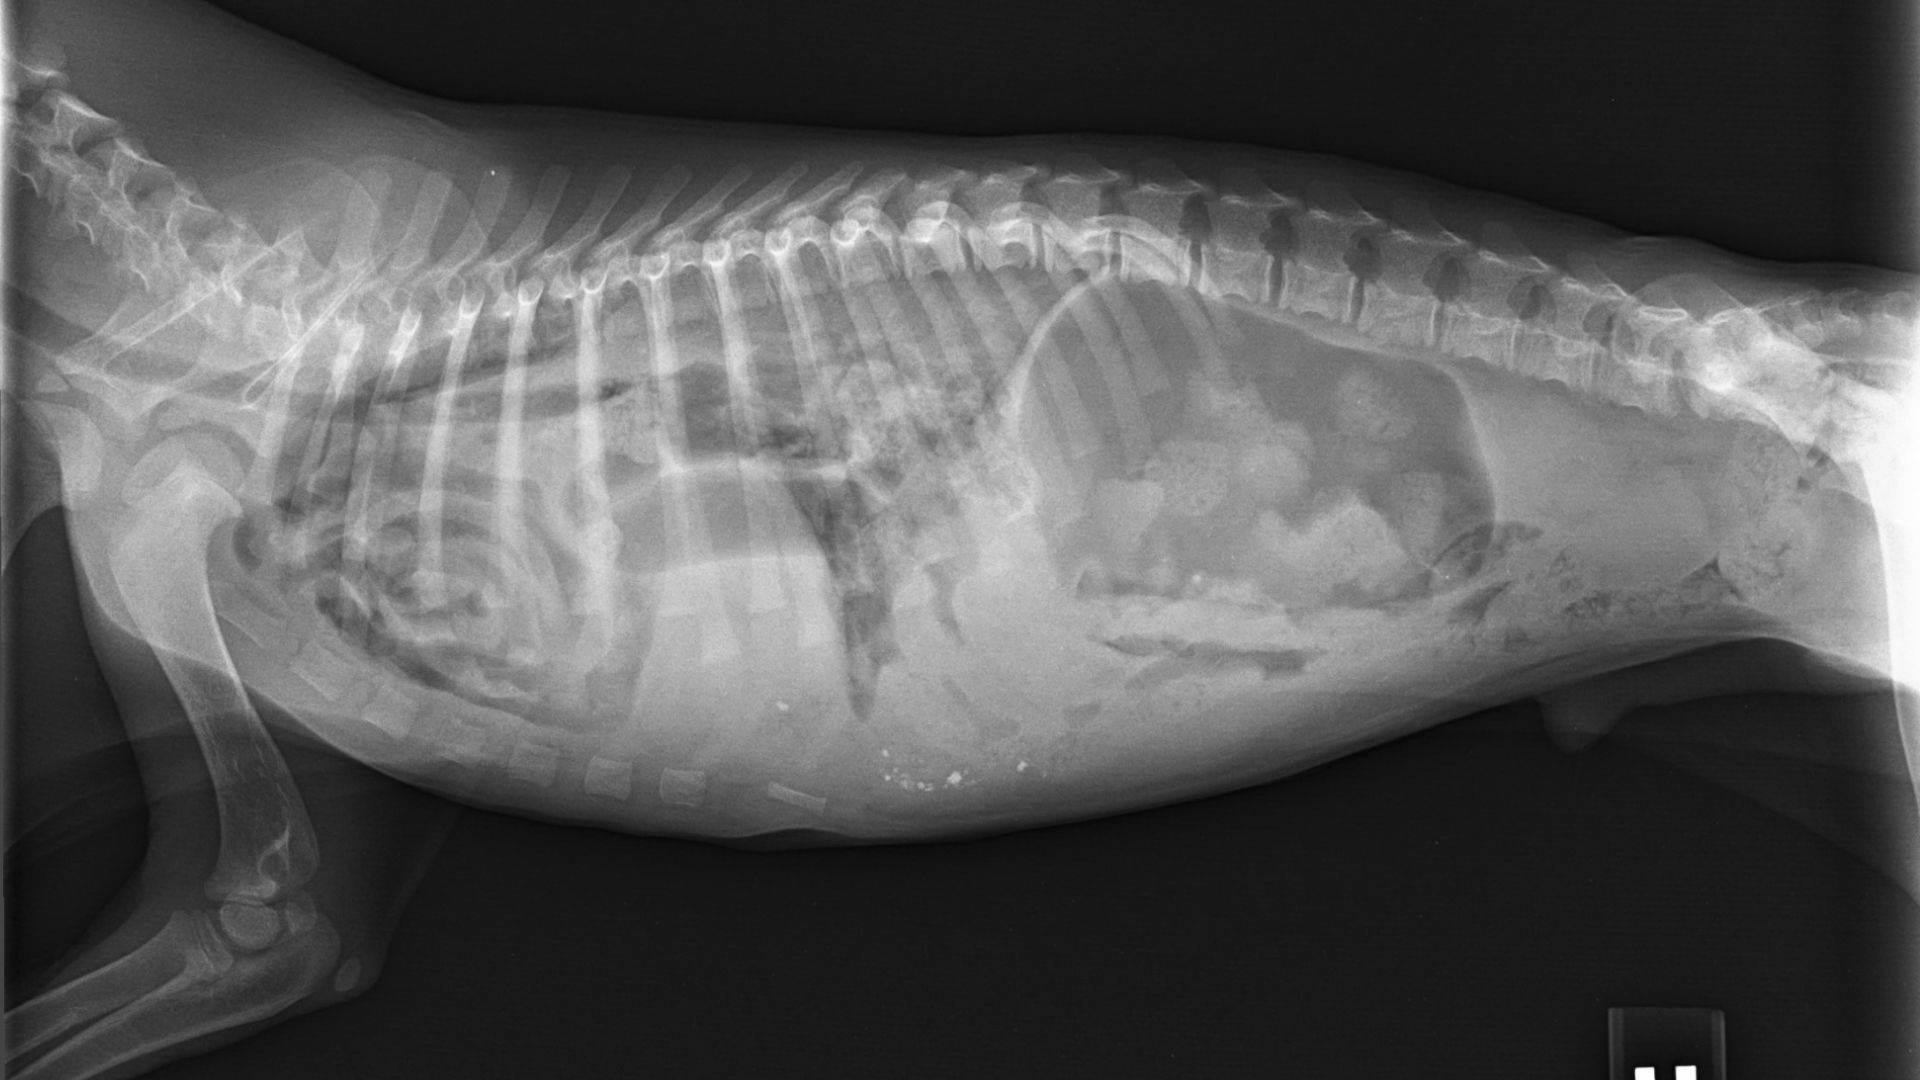

Digital X-rays provide clear, detailed images that help us diagnose fractures, foreign objects, and internal abnormalities. Our ultrasound equipment allows us to examine internal organs and detect conditions that might not be visible on X-rays. These diagnostic tools help us provide the most accurate diagnoses and appropriate treatment plans.